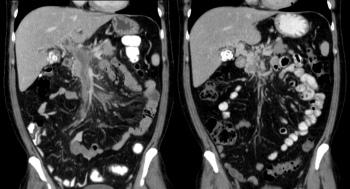

- КТ для послойного исследования мозга и выявления даже незначительных изменений;